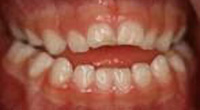

3、臼歯交叉咬合(すれ違い咬合)

・乳歯列期から治療を開始することをおすすめします。

指しゃぶりや口呼吸などによって上顎の歯列が通常に比べて狭くなっている場合、臼歯部の交叉咬合(すれ違い咬合)を引き起こすことがあります。

特に、上下正中線(前歯の真ん中のライン)が顔の真ん中のラインからずれていたり、顎が側方に偏って曲がったようになっている状態の交差咬合の場合、自然に治ることはありません。

骨格性の下顎前突と同じように、成長とともに下顎がさらに偏った状態で発育し、放っておいても症状はどんどん悪化していってしまいます。

そしてそのような交叉咬合は、歯列の変形や顎の不均衡な発育などから顔の変形(非対称)をきたし、将来、顎関節症や顎機能異常の原因となる可能性があります。

乳歯列期は上顎歯列を拡大して正常な顎やお口周りの筋肉の成長発育を促す良い時期でもありますので、この時期に治療をされることが望ましいとされています。

上顎急速拡大を3回行い鼻腔通気が改善しました。

咀嚼指導により、正中が合い、咬み合わせが安定しています。